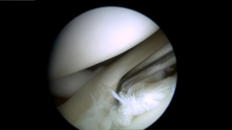

Arthroskopie =

Gelenkspiegelung

Arthroskopie = Gelenkspiegelung